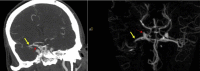

Large vessel arterial thrombosis has been reported to complicate a subset of cases of coronavirus disease 2019 (COVID-19). Thrombosis of the extracranial carotid arterial system can lead to devastating stroke in some patients with COVID-19. We have presented the case of a patient previously hospitalized with COVID-19 for oxygen supplementation who had presented after discharge with delayed stroke from a right common carotid artery and internal carotid artery thrombosis. The thrombotic occlusion resolved with antithrombotic medications and no invasive intervention. The present report highlights the complicated and heterogeneous nature of COVID-19 and provides one approach to managing the devastating complication of stroke from carotid arterial thrombosis.